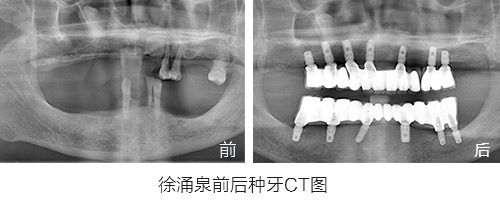

原苏州市第十七中英语老师,因为牙周炎30多岁就开始缺牙,陆陆续续共佩戴更换了5副假牙,期间多次调整,假牙带来的疼痛和牙龈发炎数不胜数。

缺牙带来最惨痛的经历:因为佩戴假牙讲课和发音十分困难,最后无奈放弃了教师职业而转岗。

种植情况:全口种植,即拔即种,植骨

种牙时间:2015年3月(已种牙1年5个月)

种植情况:全口种植